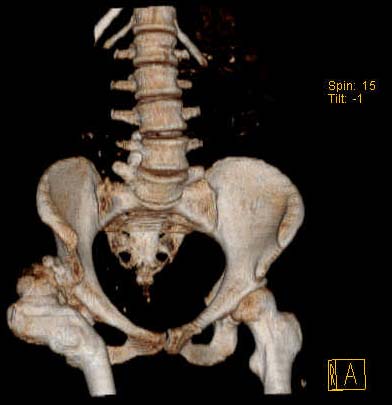

Уважаемые коллеги!Женщина, 35 летВ прошлом по поводу врожденного вывиха бедра перенесла операцию остеотомии по Шанцу

с удлинением правой ноги за счет бедра на уровне диафиза. В последнее время прогрессируют боли в правом тазобедренном суставе, порочное положение правой ноги, затруднена ходьба.Вопросы:1) Целесообразно ли эндопротезирование правого тазобедренного сустава?2) Целесообразный ли следующие действия: канал бедренной кости предполагаем вскрыть для введения ножки протеза на высоте угловой деформации, предполагаем низведение большого вертела с мышцами; протез будет подобран индивидуально, предполагается умеренная версия?В приложении рентгенограммы и трехмерная КТ.В цветном и более качественном варианте КТ размещена здесь